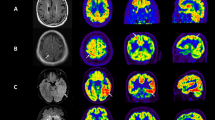

Subject 8: A 16-year old girl with known Hashimoto’s encephalopathy. The subject suffered from recurrent partial complex or tonic-clonic seizures, occasionally accompanied by auditory hallucinations. Initially euthyroid but with positive thyroid peroxidase antibodies (= 152 kIU/L; normal <6 kIU/L). The patient subsequently developed hypothyroidism. Prior to admission, her treatment included corticosteroids, anticonvulsive medication and levothyroxine. The patient was hospitalized for acute deterioration including seizures, headaches, nausea, ataxia and confusion. Blood work showed increased sedimentation rate but anti-NMDAr antibodies, anti-nuclear antibodies and anti-DNA antibodies were negative with the exception of anti-SSA (= 1.2; N < 1.0 AI). Brain PET shows mild diffuse symmetrical hypometabolism (a), more marked in the temporal lobes (b). NeuroQ™ analysis in addition to the bilateral temporal hypometabolism, demonstrates hypermetabolism in the sensorimotor cortex and anterior cingulate. NeuroQ™ analysis results overlying the adult template. Red: RRBM > upper limit of 95% prediction interval; blue: RRBM < lower limit of 95% prediction interval; green: RRBM within the 95% prediction interval

Subject 29: An 11-year old girl admitted for headaches, tonic-clonic seizures, and decreased level of consciousness. The suspected diagnosis was viral encephalitis. Blood work showed increased ESR, decreased C3 and C4 values, and negative anti-NMDAr antibodies. Serological analysis revealed anti-SSA antibodies. CSF analysis showed increased protein levels and normal glucose values. Bacterial and viral PCR analysis and cultures were negative. The findings were suggestive of neurolupus and the patient was treated with anticonvulsive medication, corticosteroids and mycophenolate mofetil. Brain PET at diagnosis showed increased uptake in the lentiform nucleus of basal ganglia. NeuroQ™ analysis demonstrates lentiform nucleus and medial temporal hypermetabolism (a). On follow-up (9 months later) neurological symptoms had subsided and qualitative brain PET was normal. NeuroQ™ analysis confirmed the hypermetabolism resolution (b). NeuroQ™ analysis results overlying the adult template. Red: RRBM > upper limit of 95% prediction interval; blue: RRBM < lower limit of 95% prediction interval; green: RRBM within the 95% prediction interval